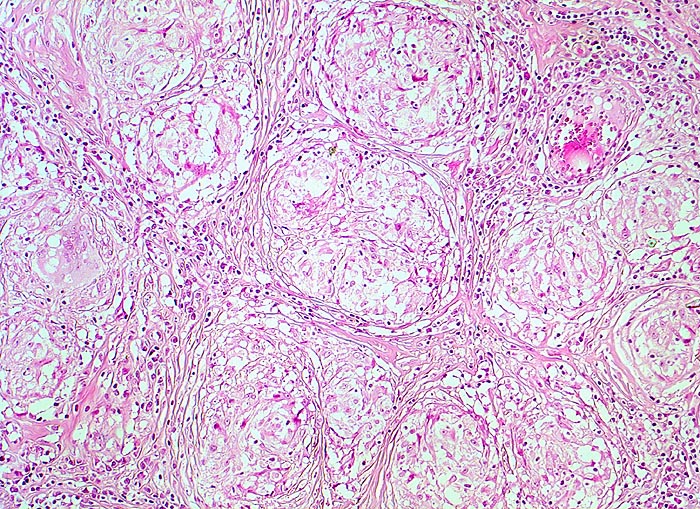

Lymphknotensarkoidose (Morbus Boeck) Granulome mit Fibrose

Lymphknoten, inguinal

Späteres Stadium einer Sarkoidose. Für Sarkoidose typische konzentrische Fibrose in der Peripherie der Granulome. Das Parenchym des Lymphknotens ist verdrängt. Die Granulome stehen Rücken an Rücken und konfluieren nicht.

Bihiläre Lymphadenopathie bei Sarkoidose. Plötzlicher Herztod.